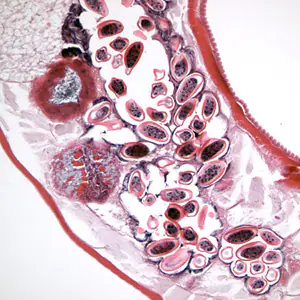

Laboratory Diagnosis

Microscopic identification of eggs collected in the perianal area is the method of choice for diagnosing enterobiasis. To improve sensitivity, collection should be done in the morning, before defecation and washing, by pressing transparent cellulose tape (“Scotch test”, cellulose tape slide test) on the perianal skin and then examining the tape placed on a microscope slide. Alternatively, anal swabs or “Swube tubes” (a paddle coated with adhesive material) can also be used for collection. Eggs can also be found, but less frequently, in the stool, and occasionally are encountered in the urine or vaginal smears. Adult worms are also diagnostic, when found in the perianal area, or during anorectal or vaginal examinations. In cases of ectopic infection, eggs may be seen in the urine or in cervicovaginal Papanicolaou smears.